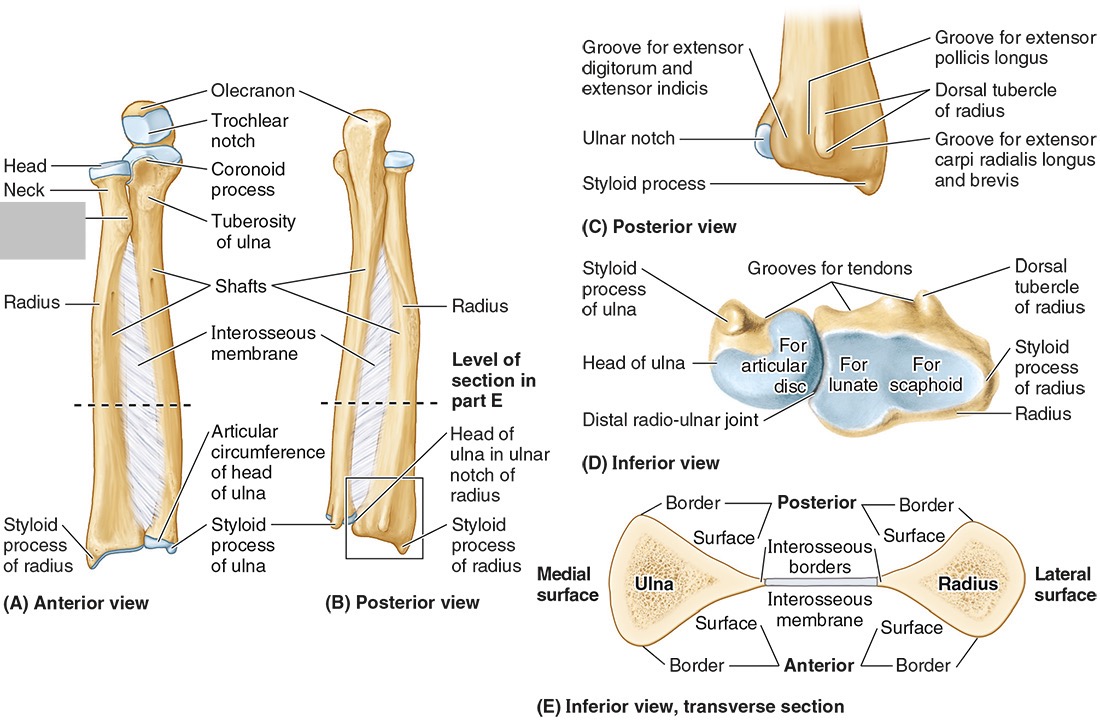

The ______ connects to the carpal bones of the hand at the wrist joint. The _____ widens distally to provide the proximal articular surface of the wrist (remember, the _____ is on thumb side of the wrist!)

(all the blanks are the same word)

Radius

The head of the radius

The neck of the radius

The radial tuberosity

The ulnar notch

The styloid process

The ____ is the medial forearm bone

Ulna

the olecranon (superior)

The coronoid processes (inferior)

The trochlear notch

The tuberosity of the ulna

The radial notch

The head of the ulna

Distal radio-ulnar joint